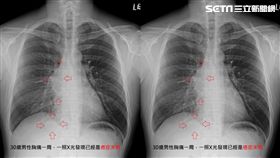

胸痛一週竟癌末!他嘆這句讓醫師心痛

台北市立聯合醫院陽明院區胸腔重症醫師蘇一峰,今(13...